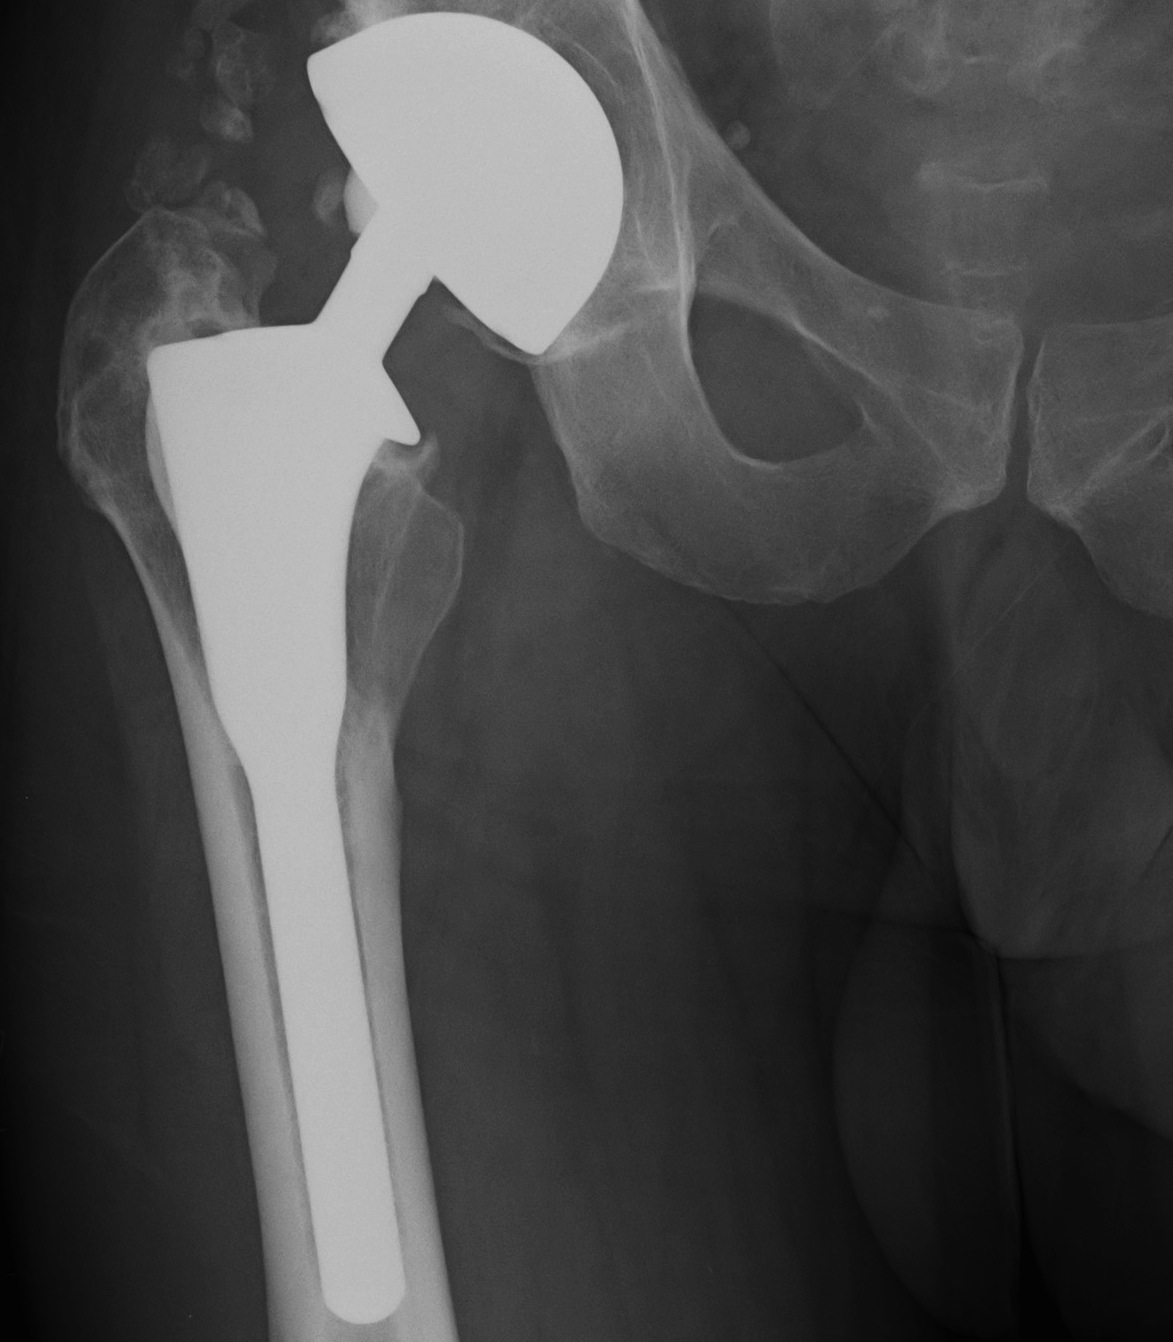

Uncemented femur

Engh classification

Types based on presence of radiolucent lines (RLL)

I.  Stable bony ingrowth

Take one year to see

A.  Spot welds at end of porous coating

B.  Absence of RLL next to porous coating

- may have RLL next to non porous coated areas

C.  Calcar atrophy secondary to stress shielding

THR Uncemented Proximal Stress ShieldingTHR Uncemented Stem Spot Weld APTHR Uncemented Stem Spot Weld Lateral

II Stable fibrous ingrowth

A.  No spot welds

B.  Parallel sclerotic lines / RLL about porous coating

C.  No migration

THR Uncemented Stem Stable sclerotic lines